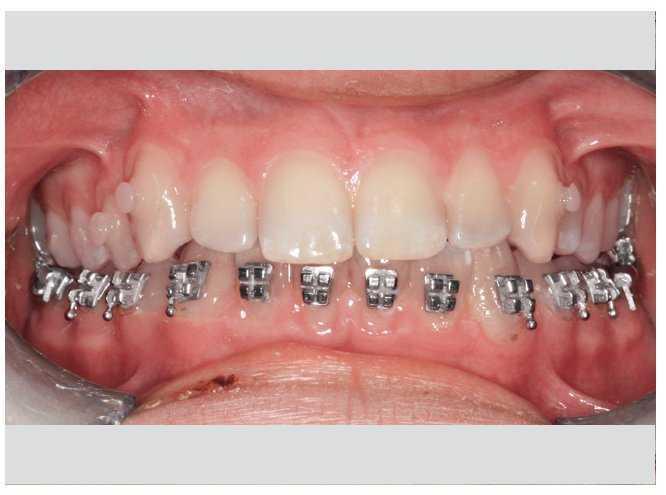

En este caso se utilizó también un sistema de brackets arco de canto labial convencional en el maxilar combinado con los mismos brackets linguales de técnica bidimensional en la mandíbula2 (fig. 20). Hicieron falta sólo dos arcos por arcada para la parte activa del tratamiento8 (fig. 21).

Figura 20. Aparato arco de canto labial en el maxilar, aparato lingual de técnica bidimensional en la mandíbula.